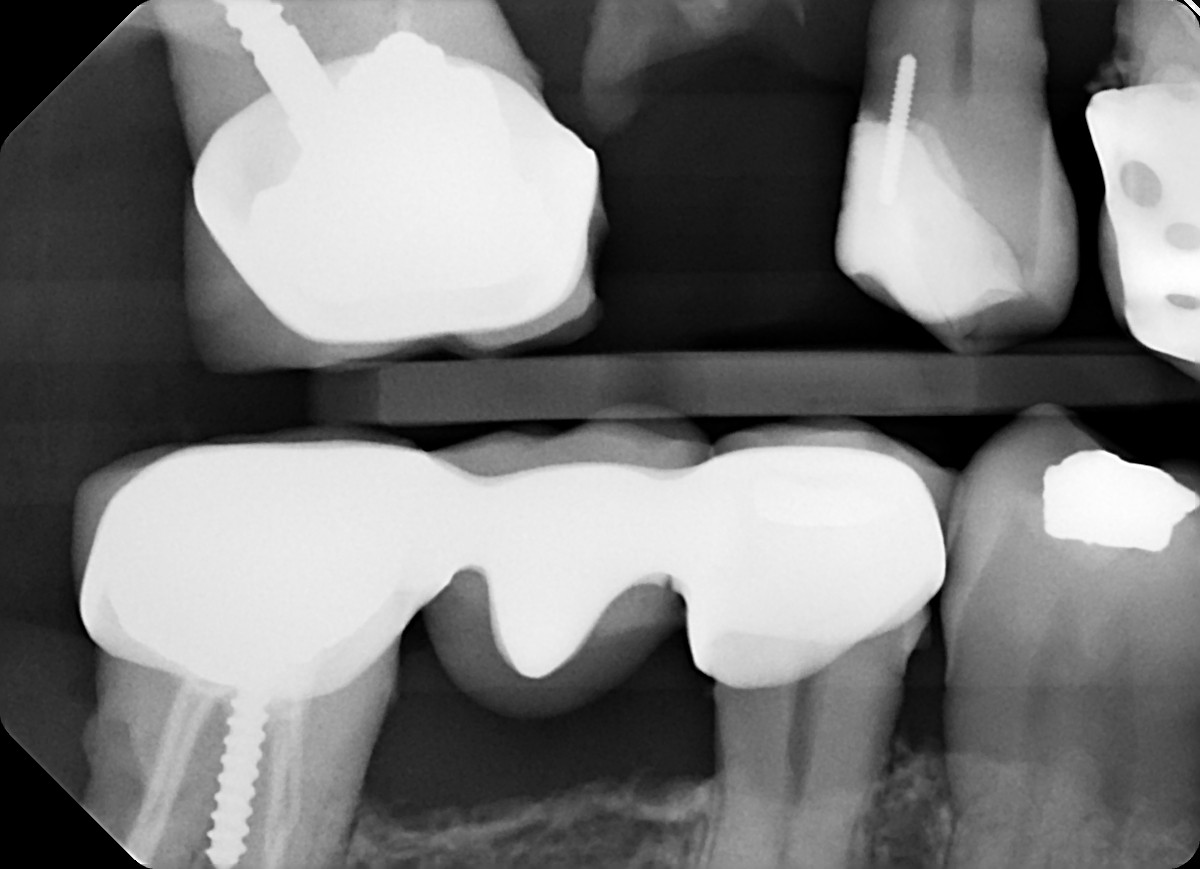

8 / 35

8. On which surface a recurrent caries can be detected?

under crowns the recurrent caries can easily become cavtated ad they are seen more radiolucent